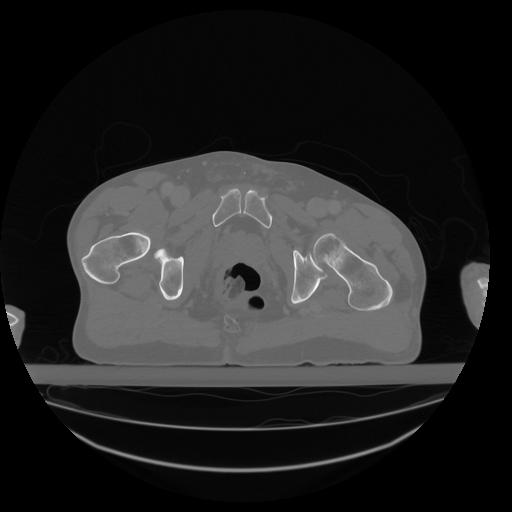

34 CUERPO,CE,Vol,1.0,CUERPO,,